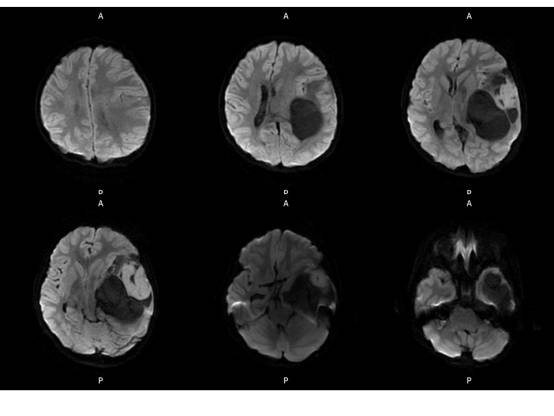

MR平扫及增强示:

左侧颞叶见大块状等长T1等长T2异常信号,FLAIR呈高新,DWI(b=1000)实质部分呈稍高信号,ADC实质部分呈等信号,边界尚清,周围脑实质受压。注入GD-DTPA后病变实质部分呈明显强化。